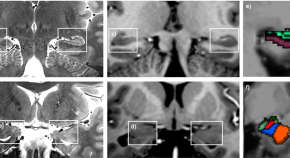

Sips and colleagues describe the onset of intravascular lymphomatosis (IVL) of the brain in a 77-year-old retired research pharmacologist with a history of anemia, pancytopenia, and a recently confirmed diagnosis of myelodysplastic syndrome (MDS). The authors discuss the mechanisms of IVL and MDS and possible relationships between the conditions, as well as a beneficial effect of treatment of IVL with high-dose combination chemotherapy and rituximab